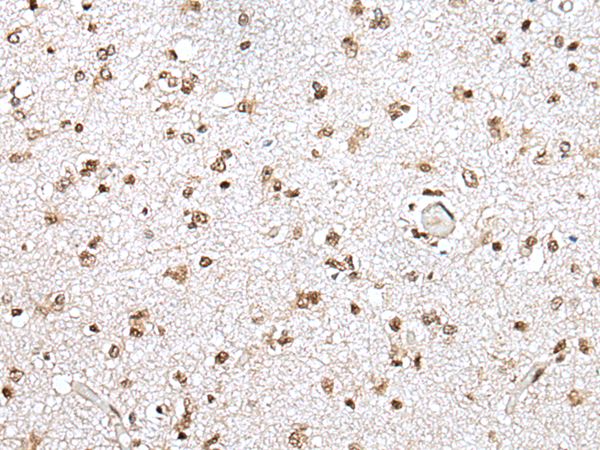

IHC positive control: |

Human lung cancer and human brain |

IHC Recommend dilution: |

25-100 |